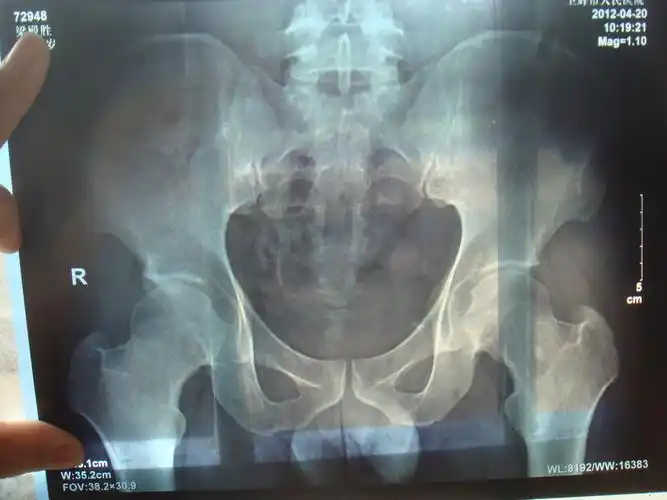

骶髂关节痛不明的腰痛屁股痛到底是啥

捉"腰"记之——骶髂关节紊乱

强直性脊柱炎发病都是从骶髂关节开始吗

第737期听医生科普骶髂关节炎

骶髂关节紊乱一例

多数腰痛根本不是腰间盘突出,而是骶髂关节疼痛,别查错了